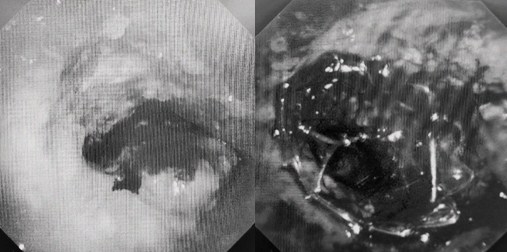

時(shí)間就是生命!了解患者病情后,歐陽海峰立刻啟動氣道梗阻緊急救治通道,協(xié)調(diào)院前轉(zhuǎn)運(yùn),急診快速入院流程。凌晨患者入院胸部CT顯示,現(xiàn)存唯一的呼吸通道在右主支氣管處,狹窄處僅約3毫米,患者命懸一線!

運(yùn)用呼吸介入技術(shù),軟硬鏡結(jié)合快速開通氣道,是患者目前唯一可行的治療方案,手術(shù)刻不容緩!但存在麻醉后氣道完全塌陷閉合、大出血、窒息等巨大風(fēng)險(xiǎn)。患者此前接連轉(zhuǎn)診3家醫(yī)院,均建議保守支持治療或轉(zhuǎn)院。歐陽海峰詳細(xì)了解患者病史,全面評估影像檢查結(jié)果后,決定盡快進(jìn)行手術(shù),組織醫(yī)護(hù)團(tuán)隊(duì)對患者進(jìn)行持續(xù)密切監(jiān)測,充分保障其術(shù)前安全。

患者入院第二天,在麻醉手術(shù)中心全力配合下,歐陽海峰帶領(lǐng)呼吸介入團(tuán)隊(duì),歷時(shí)40分鐘快速置入硬質(zhì)支氣管鏡、鏟切腫瘤,并順利植入全覆膜TTS支氣管金屬支架。患者氣短癥狀即刻緩解,為患者贏得了寶貴的后續(xù)治療機(jī)會。